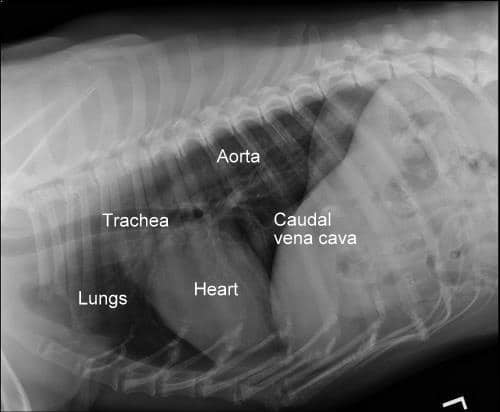

Diagnosing heart conditions in dogs typically involves a combination of clinical examination and diagnostic tests. A veterinarian may start with a physical exam, listening for heart murmurs or irregular beats, and then recommend further tests such as X-rays or an ECG to evaluate the heart’s size, shape, and electrical activity. An echocardiogram, or heart ultrasound, is particularly useful for visualizing the heart’s structure and function. Blood tests and other laboratory work can also help in diagnosing heart conditions, revealing signs of stress on the heart or related problems.